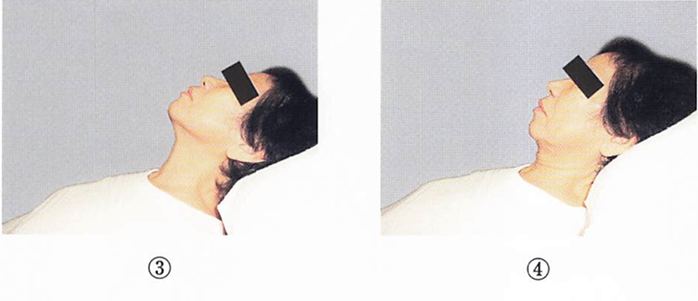

午前-87

80歳の男性。5年前に脳梗塞を発症し、現在在宅療謹中で、意識障害があるという。口臭が強いことを主訴として家族から歯科訪問診療の依頼を受けた。 歯科医師から口腔衛生管理を指示きれた。口腔清掃時の写真を別に示す。この患者に行うのはどれか。2つ選べ。

a.頭部の後屈

b.歯の動揺の確認

c.ラポールの形成

d.リクライニング位の設定

解答を見る

b.d